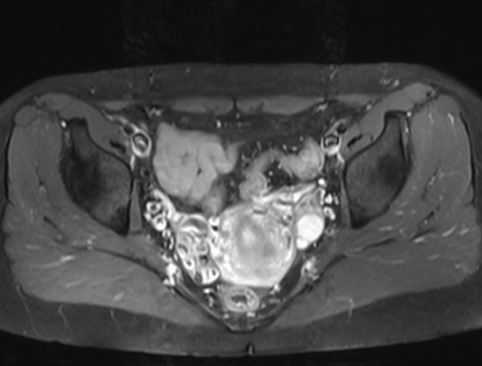

![]() 1.彩超检查 彩超检查可以发现卵巢静脉及静脉丛迂曲扩张,卵巢静脉血流缓慢或返流。 ![]() 2.增强CT及MRI检查 可显示子宫附件内迂曲、扩张的静脉血管结构。 ![]() ![]() ![]() 3.经皮导管逆行卵巢静脉造影术 目前认为是盆腔淤血综合征诊断金标准。 ![]() ![]() ![]() ![]()